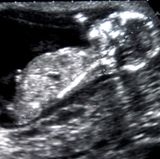

Bei Schwangeren stellt sich der Stoffwechsel um - und das Risiko für entzündetes Zahnfleisch steigt. Einige Tipps helfen dabei, Sie vor Parodontitis und Zahnausfall zu schützen.

Zahnpflege in der Schwangerschaft Besonders schonend und gründlich reinigen

Zu Beginn einer Schwangerschaft sollten Sie Ihre Zähne und Ihr Zahnfleisch vom Arzt kontrollieren und gegebenenfalls behandeln lassen. Danach können Sie weiter zur Vorsorge gehen, sollten aber möglichst größere Eingriffe vermeiden. Zähneziehen oder das Einsetzen von Kronen und Brücken schieben Sie also besser auf